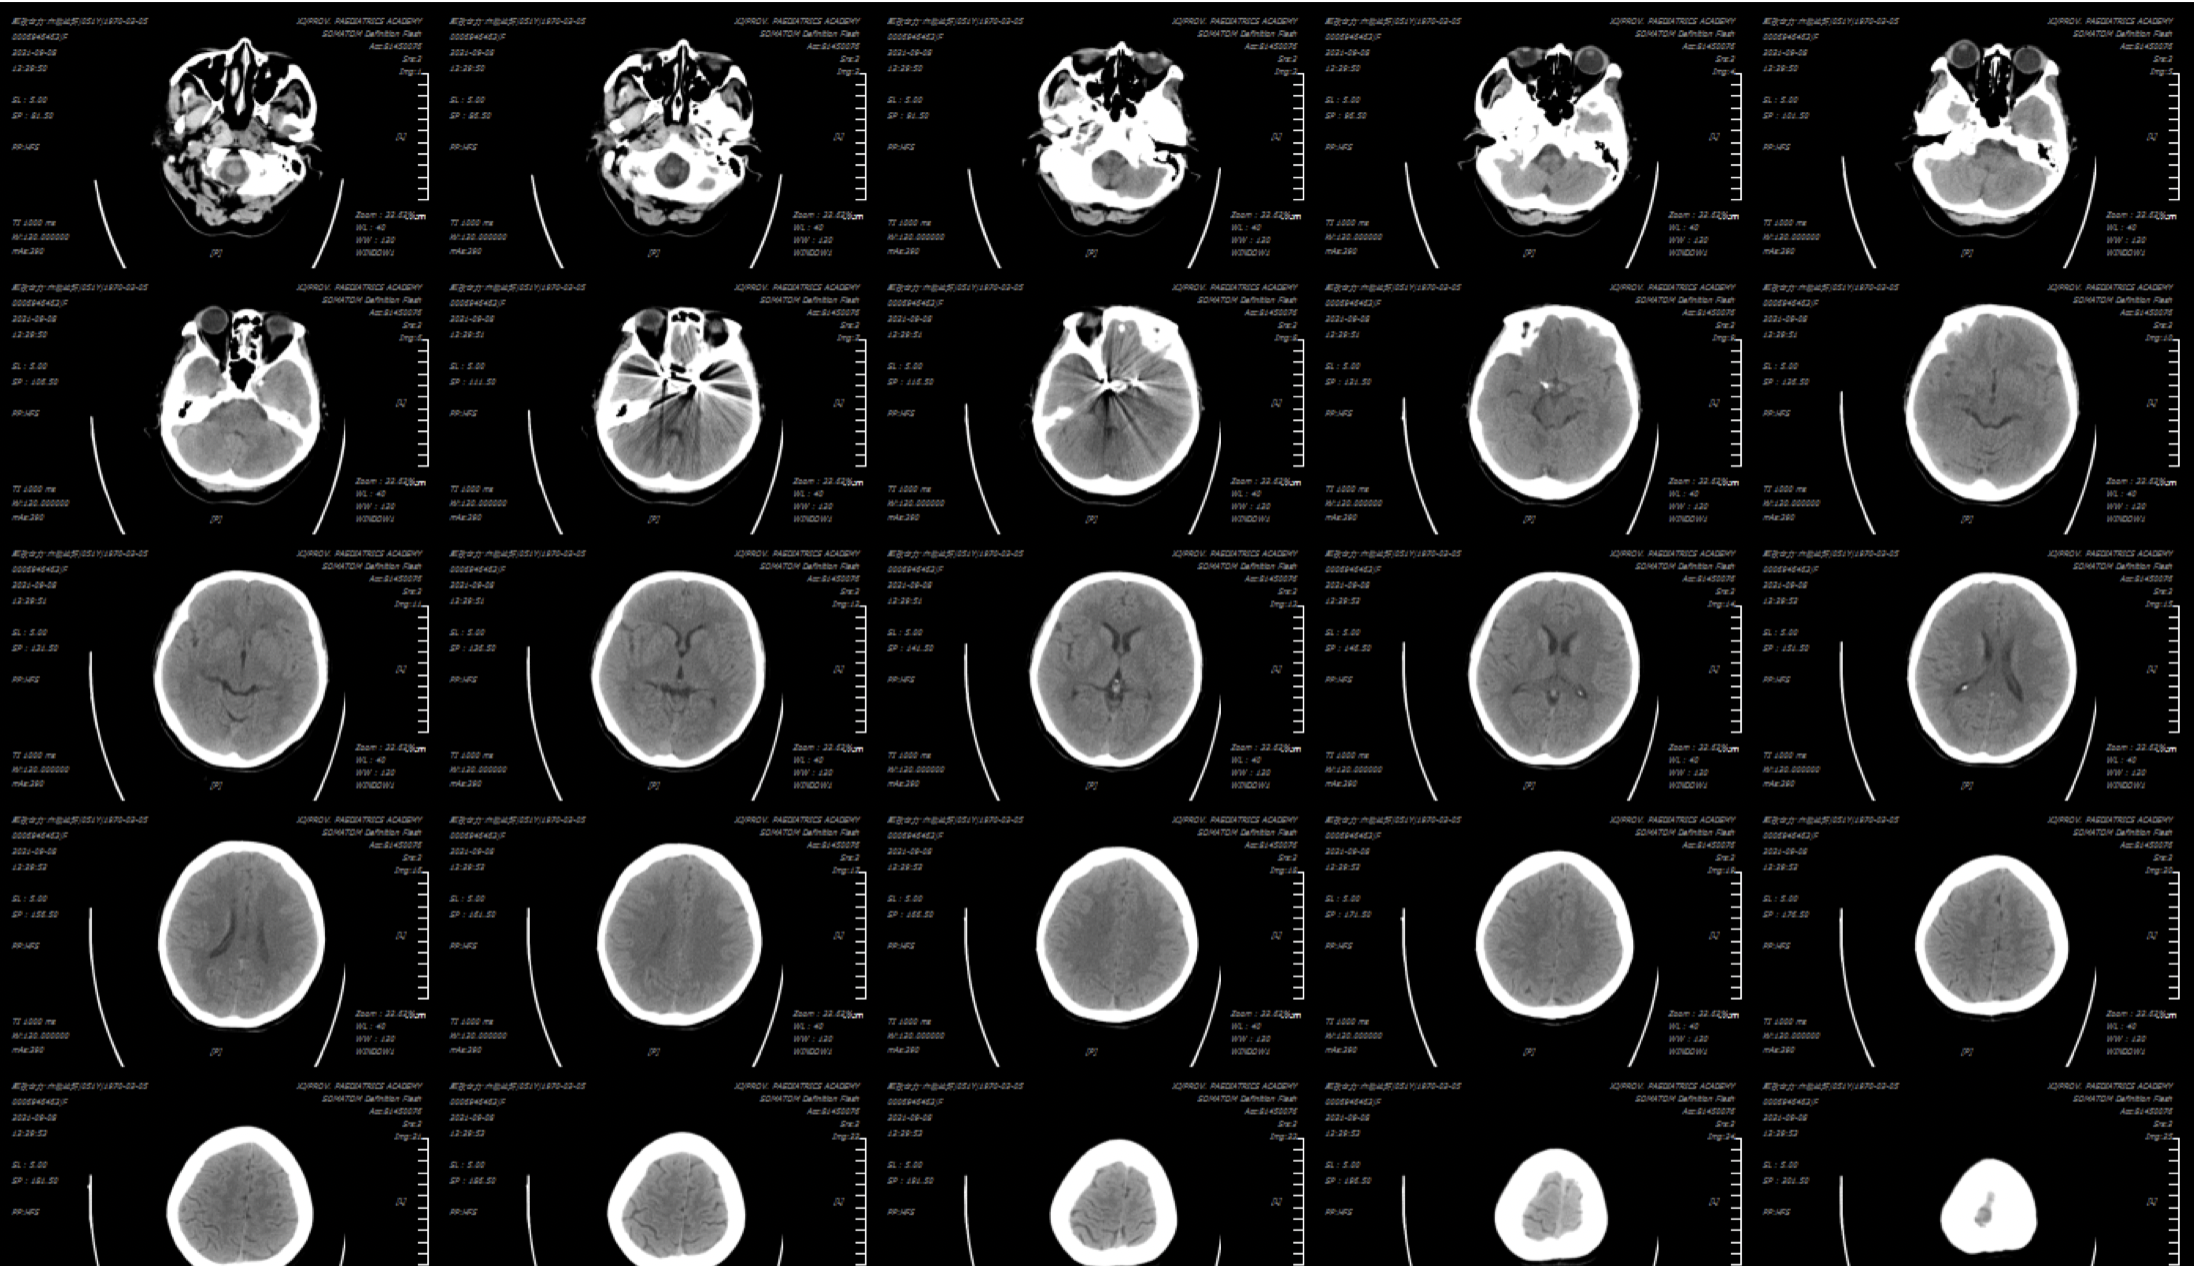

入院复查头颅CT:蛛网膜下腔少量出血!

术后复查头颅CT:颅内未见明显异常!